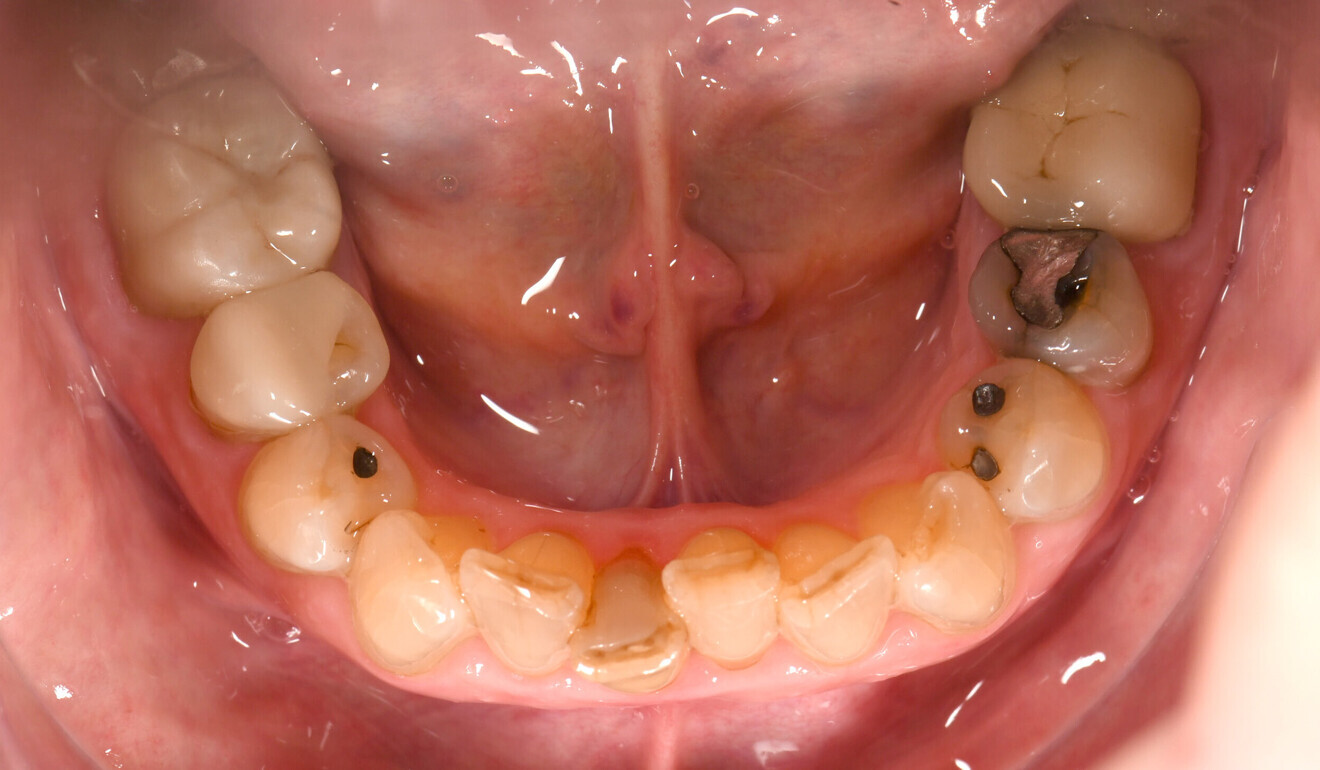

Fig. 1: Initial situation, facial view. ( All image: Wissam Dirawi)

The 71-year-old female patient presented in the clinic owing to aesthetic concerns in the maxillary anterior region. Her oral hygiene was good, and she was a non-smoker. Infraposition of the existing implant-based crown (Brånemark regular platform, Nobel Biocare) in the position of the right central incisor was evident. Moreover, gingival retraction was observed on the maxillary right lateral incisor, and the left lateral incisor (tooth #22) had a major composite filling with discoloration (Figs. 1–3). The patient expressed the desire to have the gingival margin differences adjusted and the four maxillary incisors restored with ceramic crowns for optimal aesthetics.